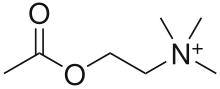

Psychoactive drugs are divided into different groups according to their pharmacological effects. Commonly used psychoactive drugs and groups are listed below:

- Stimulants (colloquially referred to as "uppers"). This category comprises substances that increase wakefulness and productivity, stimulate the nervous system, and may cause euphoria, but are not known to typically cause hallucinatory effects. Some stimulants are used medicinally to treat individuals with ADHD and Narcolepsy.

- Examples: amphetamines, caffeine, cocaine, nicotine